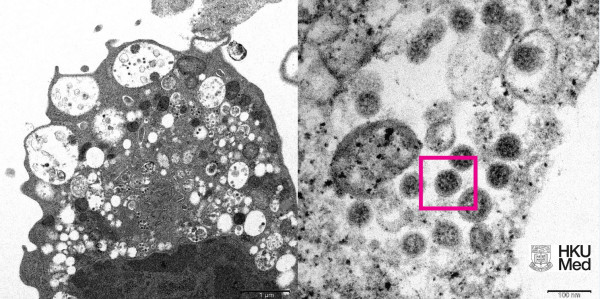

Σύμφωνα με το APA, επιστήμονες στον τομέα της υγείας, συμπεριλαμβανομένων παθολόγων και ιολόγων, κατάφεραν να λάβουν μια ηλεκτρονική μικρογραφία ενός κυττάρου (Vero E6) από το νεφρό ενός πιθήκου που μολύνθηκε με το συγκεκριμένο στέλεχος.

Στη συνέχεια το Πανεπιστήμιο δημοσίευσε τις εικόνες χαμηλής και υψηλής μεγέθυνσης.

Αριστερά, είναι η ηλεκτρονική μικρογραφία χαμηλής μεγέθυνσης κυττάρου νεφρού πιθήκου (Vero E6) μετά από μόλυνση με την παραλλαγή Omicron SARS-CoV-2. Δείχνει κυτταρική βλάβη με διογκωμένα κυστίδια που περιέχουν μικρά μαύρα ιικά σωματίδια.

Δεξιά, είναι η ηλεκτρονική μικρογραφία υψηλής μεγέθυνσης μολυσμένου κυττάρου Vero E6. Δείχνει συγκεντρώσεις ιικών σωματιδίων με αιχμές σχήματος κορώνας στην επιφάνειά τους (κόκκινο πλαίσιο).